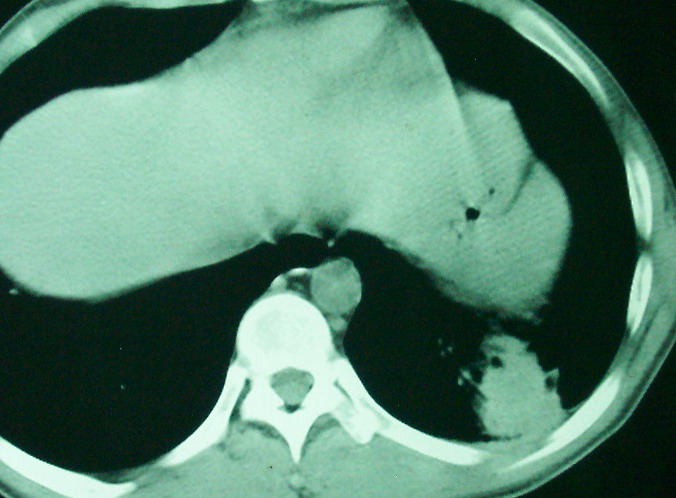

m      37y      发热   咳脓痰月余      ct肺脓肿但住院抗炎治疗后双肺内结节不知该如何解释

治疗后见左肺下野病灶较前缩小但双肺内结节影似无变化请较各位老师该如何下结论    治疗前wbc14.5 治疗后wbc 11.0

血源性肺脓肿,一般由原发感染灶引起脓毒败血症,在肺部形成小脓肿,病变变化快,容易形成肺气囊,脓气胸,主要与转移瘤鉴别,通过临床病史可分

结合病史考虑血源性肺脓肿,与转移瘤鉴别

结合临床发热,咳痰考虑为血源性肺脓肿,不过双肺结节又在肺的边缘,还是小心一点,抗炎后复查吧

左下肺病灶除了明显的厚壁空洞 气液平外,明显见壁结节,另两肺多发小结节,综合考虑:左下肺周围性肺癌伴肺内转移.

如果你仔细的同层面对比,你会发现所有的病灶均有比较明显的吸收、缩小。病变的形态,特别是脓肿的形态、壁的厚薄、内壁均有很大的变化,均在往好的方面发展。与临床症状、血像均符合,治疗效果比较显著,就是肺脓肿并双肺的化脓性炎症灶。